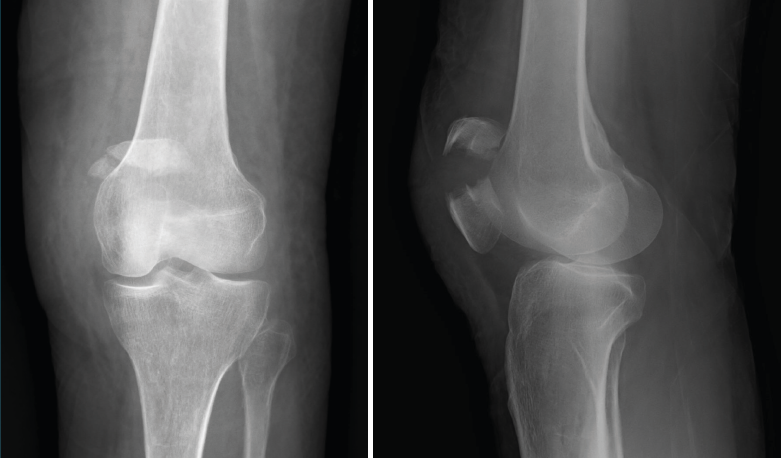

1.1.3. Rótula (Figura 3)

Figura 3. Radiografías anteroposterior y lateral de rodilla: fractura del polo superior de la rótula.